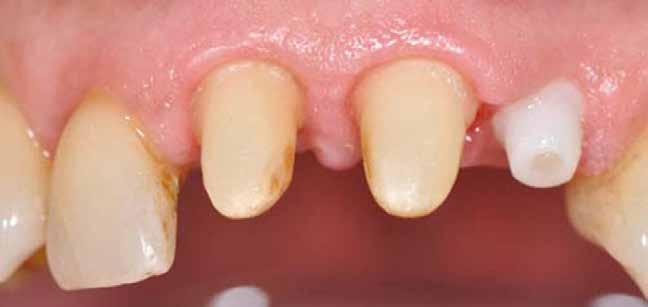

Egy 47 éves páciens jelentkezett nálunk egy alsó, hátsó foghiánnyal, ahol jelentős csontfelszívódást tapasztaltunk a moláris fogak korábbi eltávolítása miatt (1. ábra). Két implantátum körül is volt ínyrecesszió, illetve a keratinizált íny mennyisége minimális volt (kevesebb, mint 1 mm). 4 hónappal az implantációt követően ínykorrekciót végeztünk.

A páciens mobilis implantátum körüli lágyszövettel rendelkezett, a keratinizált íny szélessége kevesebb volt, mint 1 mm és a nyálkahártya vastagsága nem érte el a 2 mm-t. Az ínyszél az implantátum platform vonalában volt. Az alábbi műtéti technikával jelentős javulást sikerült elérnünk az implantátum körüli lágyszövetek minőségében és a nem elmozduló keratinizált szövet szélesedett 4 mm-rel. A Kígyótechnikánál alkalmazott elforgatott lebeny a szabad keratinizált íny lebeny előnyeivel növeli a nem elmozduló nyálkahártya szélességét az implantátum körül. Biztosítja továbbá a jó vérellátást és a nyeles lebeny stabilitását, ami kisebb mértékű zsugorodást eredményez, mint egy szabad lágyszövet lebenyátültetésnél (29).

Az implantátum körüli lágyszövet defektusok teljes rehabilitációját sikeresen elérhetjük egy második műtéttel elvégzett lágyszövet augmentációval. A javasolt módosított, nyelezett Kígyó lebeny technika jelentősen javított az implantátum körüli lágyszöveteken, mind szélesség, mind vastagság tekintetében egy, kettő és öt évvel a műtét után is egyaránt tartós maradt az eredmény. Az előnyei a következők: nincs szükség második sebre (távoli donorterületre), jobb a vaszkularizáció, nincs nekróziskockázat, gyorsabb a gyógyulás mind a donor, mind a recipiens területen, nincs nagyobb fájdalom vagy diszkomfort. Hosszú távú utánkövetéses, randomizált kontrolltanulmányokra van szükség ahhoz, hogy megállapítsuk, hogy valóban egy tartós, megbízható módszerről van szó.